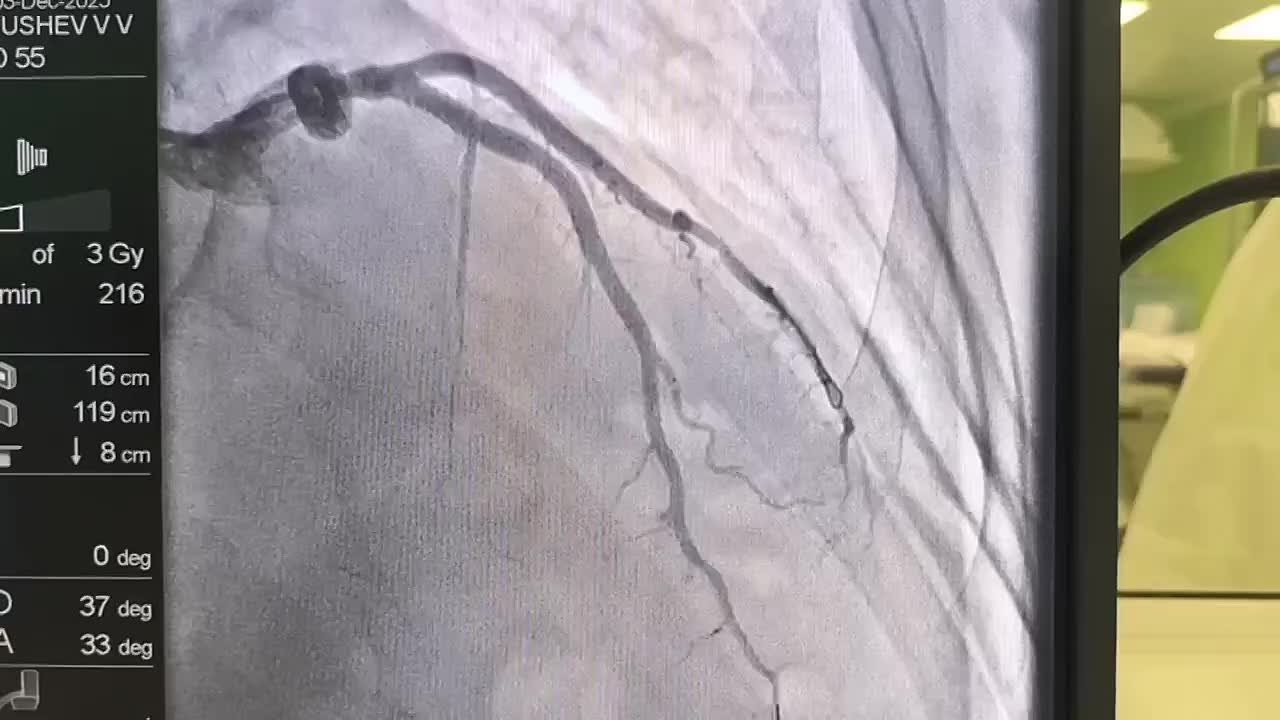

Вчера медики Республиканской больницы спасли жизнь 55-летнему мужчине, вовремя проведя экстренное стентирование коронарных артерий.

Особая благодарность бригаде скорой помощи и врачам-рентгенхирургам. Именно их высочайший профессионализм и слаженная работа позволили в сжатые сроки восстановить кровоток и спасти миокард, сообщает Минздрав Республики Алтай.